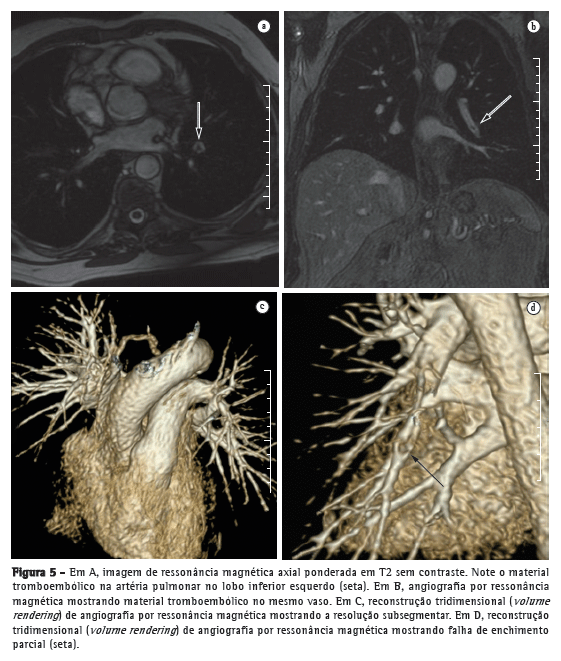

Estima-se que todo ano nos Estados Unidos haja aproximadamente 150.000 novos casos de nódulos pulmonares observados em radiografia simples de tórax.(9) Uma meta-análise recente relatou que a TC dinâmica e a RM, ambas as quais são métodos não invasivos, são igualmente acuradas para fazer a distinção entre nódulos pulmonares solitários benignos e malignos e que as diferenças entre os dois exames são insignificantes.(10) Os autores da meta-análise constataram que, para os 10 exames com TC dinâmica, a RM apresentou sensibilidade combinada de 93% (IC95%: 0,88-0,97) e especificidade combinada de 76% (IC95%: 0,68-0,97).(10) Koyama et al.(11) relataram que a RM de pulmão sem contraste é tão eficiente quanto a TC com multidetectores e cortes finos para detectar nódulos malignos. Os autores também constataram que a taxa global de detecção de nódulos em cada sequência de RM (82,5%) foi significativamente menor que a da TC com multidetectores (97,0%), embora não tenha havido diferença significativa entre as duas técnicas no que tange à taxa de detecção de nódulos malignos.(11) A Figura 1 mostra uma comparação de imagens obtidas com as duas modalidades.

Sistema de estadiamento tumor-nódulo-metástase